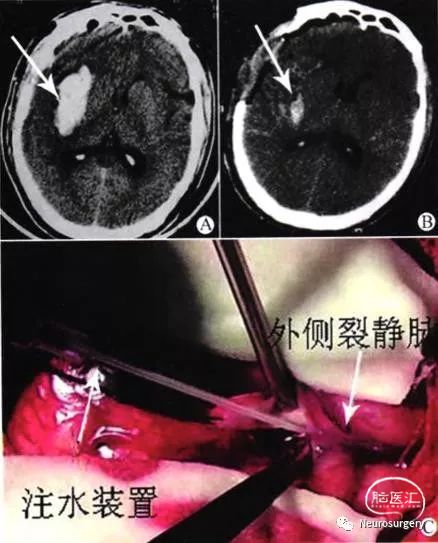

图1 右侧基底节区脑内血肿手术前后CT图像及术中分离外侧裂之图像

患者均采用全身麻醉,根据患者术前意识状况、血肿量及CT片脑中线移位程度,取血肿侧标准翼点或扩大翼点入路。术前根据CT图像,在头皮上画出血肿及外侧裂在体表的投影。开颅后在显微镜下切开硬脑膜,于侧裂的额侧三角部用尖刀将蛛网膜切开一小口,然后由手控带有钝针头的20ml注射器将生理盐水经小口注入侧裂蛛网膜下腔(见图1C),一般注入20 ml生理盐水后就能很好的进一步向远端打开侧裂,一般打开侧裂表面长约6 cm的蛛网膜即可,同样在侧裂腔内采用水分离技术能够进一步帮助分开外侧裂深面,直至岛叶,用带有明胶海绵的湿绵片覆盖额叶及颞叶岛盖部,用吸引器头及双极电凝代替脑压板牵拉额叶及颞叶就能充分显露岛叶,根据血肿位置,选择岛叶无血管区(必要时可游离大脑中动脉)电凝并切开长约1—1.5 cm即可深入血肿腔,清除血肿中央部分血肿后,同样采用水分离技术向血肿腔注生理盐水,血肿很容易与周围脑组织分离而自行排出,一般清除血肿后无渗血,创面贴覆止血纱布即可。血肿清除后脑压明显下降,用人工脑膜减张修补缝合,根据术前意识状况决定骨瓣去留,血肿破入脑室较多者同时行脑室外引流。

应用水分离技术解剖分离外侧裂时,先在侧裂较宽处(一般选择侧裂的额侧三角部)用尖刀将蛛网膜切开一小口,然后由手控带有钝针头的20 ml注射器将生理盐水经小口注入侧裂蛛网膜下腔,待侧裂处蛛网膜下腔拓宽后,用双极电凝镊子撕开蛛网膜,对于蛛网膜较厚且坚韧者用显微尖刀剪开,同样在侧裂腔内采用水分离技术能够进一步帮助分开外侧裂深面,直至岛叶,用带有明胶海绵的湿绵片覆盖额叶及颞叶岛盖部,用吸引器头及双极电凝代替脑压板牵拉额叶及颞叶岛盖部,就能充分显露岛叶,并能清楚看到大脑中动脉走行,然后用湿绵片保护好大脑中动脉,从而避免过度牵拉或双极电凝误伤血管,导致术后脑梗死,根据血肿位置,选择岛叶无血管区电凝并切开长约l~1.5 cm即可深入血肿腔,清除血肿中央部分血肿后,同样采用水分离技术向血肿腔注生理盐水,这时血肿很容易与周围脑组织分离,且随着脑搏动自行排出,这样就避免了直接用吸引器清除周围血肿时因吸力控制不佳而损伤正常脑组织及基底节区的小穿支血管。